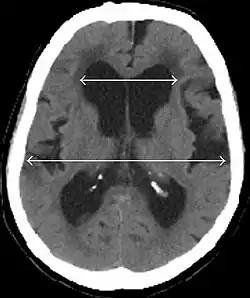

Diagnostisch sollte bei vorliegender klinischer Symptomatik ein CT oder alternativ MRT des Gehirns angefertigt werden. Eine (krankhafte[26]) Erweiterung der inneren[27][26](besonders der Vorder- und Temporalhörner[26]) und äußeren[26] (besonders der Sylvischen Fissur[26]) Liquorräume ist typisch.

Hinweise auf einen Normaldruckhydrozephalus sind:

- Evans-Index(maximaler Innendurchmesser der Frontalhörner der Seitenventrikel dividiert durch maximalen Innendurchmesser des Schädels) > 0,3[27] auf Höhe des Foramen Monroi[28] im axialen Schnitt[28], das heißt eine Erweiterung der Seitenventrikel